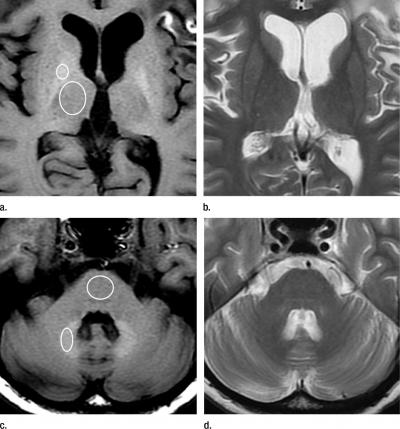

However, in recent years, clinicians in Japan noticed that patients with a history of multiple administrations of Gd-CM showed areas of high intensity, or hyperintensity, on MRI in two brain regions: the dentate nucleus (DN) and globus pallidus (GP). The precise clinical ramifications of hyperintensity are not known, but hyperintensity in the DN has been associated with multiple sclerosis, while hyperintensity of the GP is linked with hepatic dysfunction and several diseases.

To learn more, the researchers compared unenhanced T1-weighted MR images (T1WI) of 19 patients who had undergone six or more contrast-enhanced brain scans with 16 patients who had received six or fewer unenhanced scans. The hyperintensity of both the DN and the GP correlated with the number of Gd-CM administrations.

"The hyperintensity of DN and GP on unenhanced T1WI may be due to gadolinium deposition in the brain independent of renal function, and the deposition may remain in the brain for a long time," Dr. Kanda suggested.